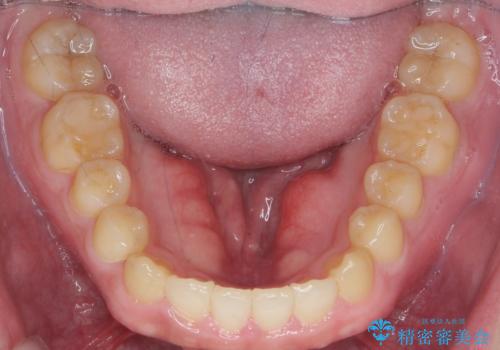

- 前歯の噛み合わせが反対になっていること、前歯の見た目の改善を希望され来院されました。

詳細な矯正検査の結果、顎の歪みが見られたため大きく歯を動かす治療ではなく前歯を主に並べることで前歯の前後関係を改善していきます。

前歯を主に動かす部分矯正であることからマウスピース矯正インビザラインによる治療を計画します。